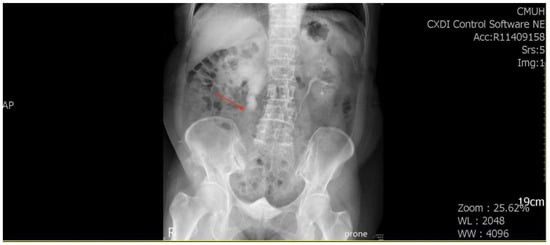

She underwent ureterorenoscopic surgery under the impression of a ureteral stone with obstruction. During the operation, a small stone was found with a tumor-like lesion below the stone. An endoscopic biopsy was performed during the operation, and the pathology report was chondrosarcoma. The tumor was heterologous and composed of epithelioid cell and chondrosarcoma components. The tumor’s immunoprofile was CK (+, only in the epithelioid tumor cells), vimentin (+, in both the epithelioid cells and chondrosarcoma cells), S100 (+, only in the chondrosarcoma cells), and GATA3 (−) (Figure 2). The picture was compatible with carcinosarcoma. Computed tomography (CT) of the abdomen revealed a tumor mass obstructing the upper ureter with proximal dilatation (Figure 3).

Figure 3. Computed tomography of the abdomen revealed a tumor (arrowhead) in the right upper ureter with proximal dilatation. (A) Coronary view; (B) Sagittal view.